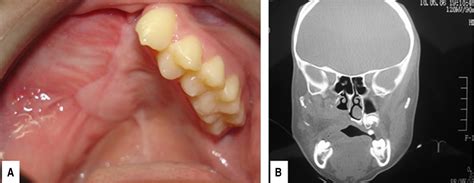

Clínicamente el FO se caracteriza por ser una lesión asintomática, de tamaño variable y crecimiento lento que genera expansión ósea. La mucosa que recubre la lesión es normal.

Sus características radiográficas varían de acuerdo a su evolución, caracterizándose por ser una lesión radiolúcida en un comienzo, presentando progresivamente zonas de radioopacidades en su interior, para finalizar como una lesión completamente radioopaca rodeada por un halo radiolúcido.

El diagnóstico de presunción es clínico radiológico mediante ortopantomografía y TAC. Radiográficamente en la ortopantomografía (OPM) como en la tomografía axial computarizada (TAC), consiste en una lesión bien circunscrita, de crecimiento expansivo, heterogénea que entremezcla áreas radiopacas calcificadas (350-1000 unidades Houns-field (HU), con zonas de menor densidad (10-40 HU) (2). El diagnóstico diferencial es con la displasia fibrosa y meningiomas.

TAC mostrando un fibroma osificante.

Se presenta un caso de una niña de 10 años de edad con aumento de volumen en hemicara izquierda a expensas del maxilar superior. En los controles clínico y radiológicos posterior a la recidiva a los dos y cinco años, se encuentra libre de lesión.

Caso clínico: Paciente género masculino de 22 años de edad, acude al servicio de cirugía maxilofacial del Hospital San José derivado por su odontólogo por un aumento de volumen indoloro en relación a cuerpo y rama mandibular izquierda de evolución indeterminada.